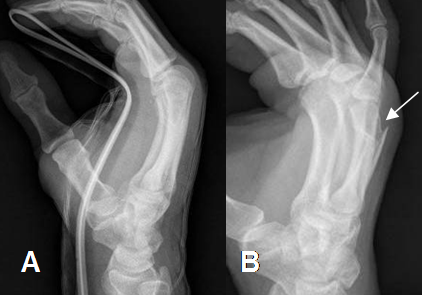

Fig 8. Fractura de metacarpiano.

A: Rx lateral, sin cambios detectables.

B: Rx oblicua, donde se identifica fractura oblicua del 4º metacarpiano.